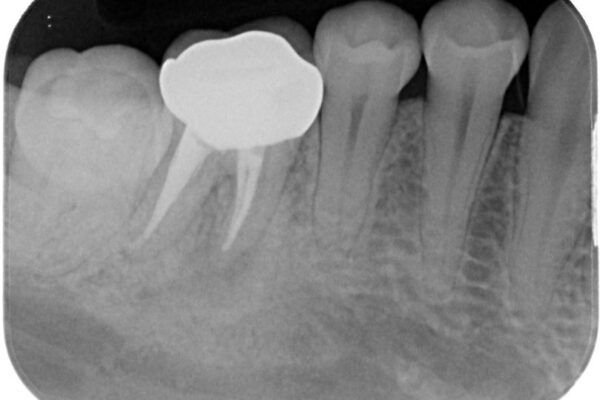

「以前に根管治療をした歯が、噛むと違和感がある」とのことでご来院された患者様の症例です。 患者様は、数年前に他院で根管治療を受けたとのことでしたが、被せもの(クラウン)は装着されていない状態でした。 噛んだときの違和感が慢性的にあり、食事中も気になるとのことで当院にご相談いただきました。 レントゲン検査では、根の先端に透過像(根尖病変の可能性)が見られ、過去の治療ではラバーダム防湿が使用されていなかったそうです。

• ラバーダム使用で再感染リスクを抑えた再根管治療+精密な補綴による長期安定を実現 治療前画像